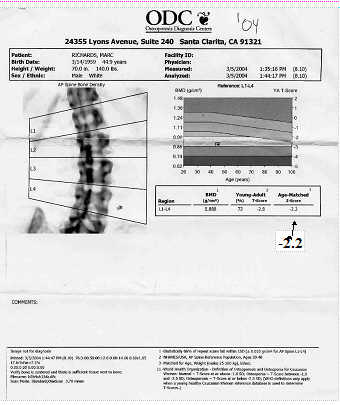

2004: I started standing daily and walking several times a week. I also started taking Fosamax weekly and extra calcium daily. A score of -2.2 still means osteoporosis, but it's becoming less of a problem.

Here's a graph to illustrate T-score results::